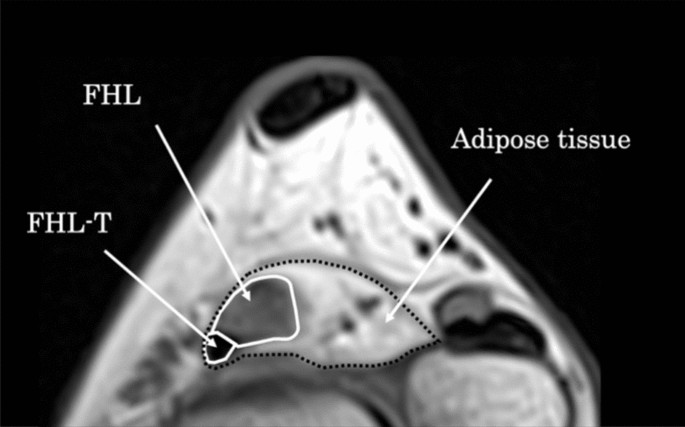

On axial MRI images (horizontal plane), the FHL tendon at the level of the talocrural joint in all 40 feet was surrounded by oval-shaped adipose tissues, while the ligament and posterior articular capsule of the talocrural joint were in the deep layer (Fig. 5). When the CSAs of the FHL tendon and adipose tissue were measured using the trochlea of the talus as an index, the median CSA of the FHL tendon was 14.4 mm2 (11.7–16.7 mm2) and that of the adipose tissue was 120.5 mm2 (100.3–149.4 mm2) (Fig. 6). Furthermore, the median volume of adipose tissue was 963.3 mm3 (896.2–1115.6 mm3).

Method of measuring the cross-sectional area of adipose tissue around the flexor hallucis longus tendon. The cross-sectional area of adipose tissue was defined as the difference between the cross-sectional area of the flexor hallucis longus muscle and that of adipose tissue. Black dotted line: adipose tissue trace section. White line: flexor hallucis longus trace section. FHL, flexor hallucis longus; FHL-T, flexor hallucis longus tendon.